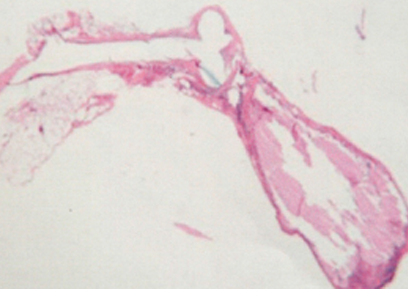

Cone주변의 콜라겐 생산 현상

Cone의 단면(이동분)및 피부조직을 파고들어 자라고 있는 새로운 섬유 중 조직을 보여주는 전자 현미경 조직 사진

Suture 및 Cone을 촬영한 전자 현미경 사진

사진은 중심에 매듭과 부드러운 콜라겐 캡슐로 둘러싸여 보존 되어진 Suture